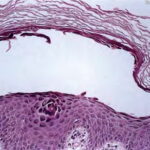

Histopathology. The earliest change consists of acantholysis in the upper epidermis, within or adjacent to the granular layer, leading to a subcorneal bulla in some instances . More commonly, enlargement of the cleft leads to detachment |

of the stratum corneum without bulla being seen. The number of acantholytic keratinocytes is usually small, often requiring a careful search to identify them. Secondary clefts may develop, leading to detachment of the epidermis in its mid level. These clefts may extend to above the basal layer, rarely giving rise to limited areas of suprabasal separation. In the setting of a subcomeal blister, dyskeratotic granular keratinocytes are diagnostic for this disorder. Eosinophilic spongiosis may be prominent with intraepidermal eosinophilic pustules. Thus, the histologic features of pemphigus foliaceus may have three pattems: {a} eosinophilic spongiosis; {b} a subcorneal blister, often with few acantholytic keratinocytes; and {c} a subcorneal blister with dyskeratotic granular keratinocytes , diagnostic of this disorder. The character of the inflammatory infiltrate is variable and depends on the age of the lesion, whether a blister is present, whether the superficial portion of the epidermis has been detached, and whether there is impetiginization or necrosis of the blister roof. |